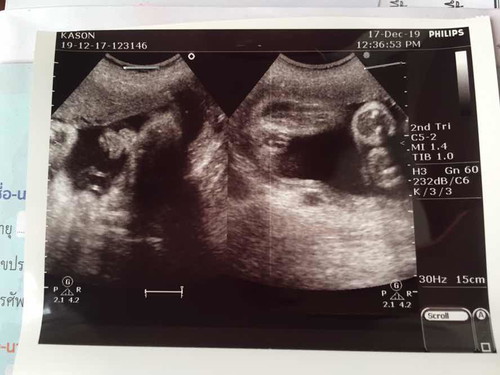

31 Week ลูกสาว.

ตามเกณฑ์ต้องน้ำหนัก 1,590. อันนี้ซาวด์ได้ 1,450. แอบเป็นกังวลนิดหน่อยว่าลูกจะตัวเล็ก. แม่ๆคิดว่าตัวเล็กมั้ยค่ะหรือปกติ. แล้วในใบซาวด์ก้ดูไม่ออกว่าลูกคือส่วนไหนในภาพ 555 (ถามแม่ๆท่านอื่นเพื่อความสบายใจนะคะ. งดดราม่า ??)